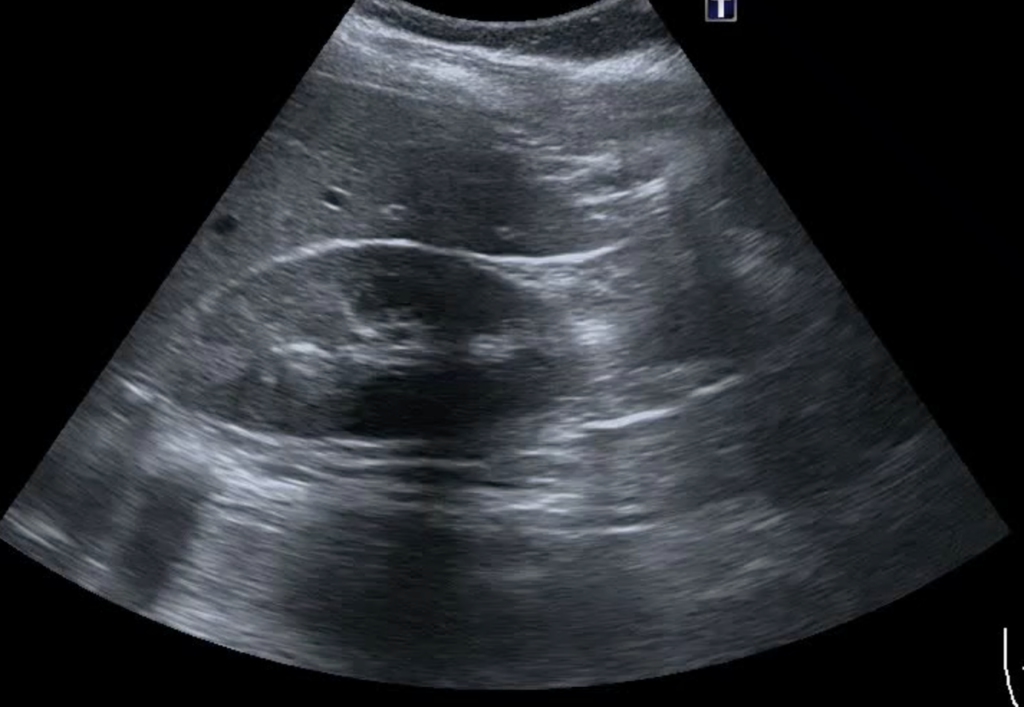

Jednym z mostów łącząc świat nauk podstawowych, do jakich bezsprzecznie należą anatomia prawidłowa i fizjologia, ze światem decyzji klinicznych jest ultrasonografia.

Koncepcja Point-of-Care w swoich pierwotnych założeniach jest poszukiwaniem odpowiedzi na pytania kliniczne z wykorzystaniem wszystkich dostępnych środków i sprzętów. Jedną z jest jej odmian jest ultrasonografia Point-of-Care.

Jako badanie kontekstowe stanowi poszerzenie badania przedmiotowego. Praktyka pokazuje, że POCUS wnosi cenne informacje kliniczne pozwalające skierować terapię na zupełnie nowe tory.